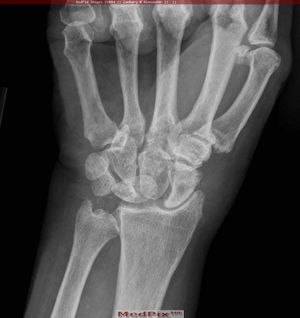

엘러스-단로스 증후군의 근골격계 증상으로는 과도하게 신전되는 관절, 관절의 불완전한 염좌, 전위, 탈구, 확장[170]이 나타나기 쉬운 과가동성 관절이 있다.[8][15] 흉부 콘센트 증후군, 조기에 진행된 관절염,[171] 만성 퇴행성 관절질환,[44] 손가락의 백조 목 변형,[172][45] 손가락의 단추 구멍 변형이 나타날 수 있다.[46] 힘줄 또는 근육의 끊어짐,[173] 척추측만증 (척추의 곡률), 전만증 (흉부 혹),[174] 척추 후만증 (흉추 굽음), 척수 신경 유착 증후군, 두개경추 불안정성 (CCI), 환추 축추 불안정성과 같은 척추 변형이 나타날 수도 있다.[47][48] 골다공증과 골감소증 또한 EDS와 증상성 관절 과운동성과 관련이 있다.[49][50]

엘러스-단로스 증후군의 근골격계 증상으로는 과도하게 신전되는 관절, 관절의 불완전한 염좌, 전위, 탈구, 확장[170]이 나타나기 쉬운 과가동성 관절이 있다.[8][15] 흉부 콘센트 증후군,조기에 진행된 관절염,[171] 만성 퇴행성 관절질환,[44] 손가락의 백조 목 변형,[172][45] 손가락의 단추 구멍 변형이 나타날 수 있다.[46] 힘줄 또는 근육의 끊어짐,[173] 척추측만증 (척추의 곡률), 전만증 (흉부 혹),[174] 척추 후만증 (흉추 굽음), 척수 신경 유착 증후군, 두개경추 불안정성 (CCI), 환추 축추 불안정성과 같은 척추 변형이 나타날 수도 있다.[47][48] 골다공증과 골감소증 또한 EDS와 증상성 관절 과운동성과 관련이 있다.[49][50]심각한 근육통 (근육통)과 관절통[175]이 나타날 수도 있다.[51] 한 다리로 서 있을 때 반대쪽 골반이 떨어지는 트렌델렌버그 징후가 자주 나타난다.[52][176] 무릎에 통증을 동반하는 덩어리가 생기는 오스굿-슐라터병 또한 흔하게 나타난다.[53][177] 유아의 경우, 보행이 지연될 수 있고 (18개월 이후), 기어 다니는 대신 엉덩이로 기어 다니는 모습이 나타난다.[54][178]